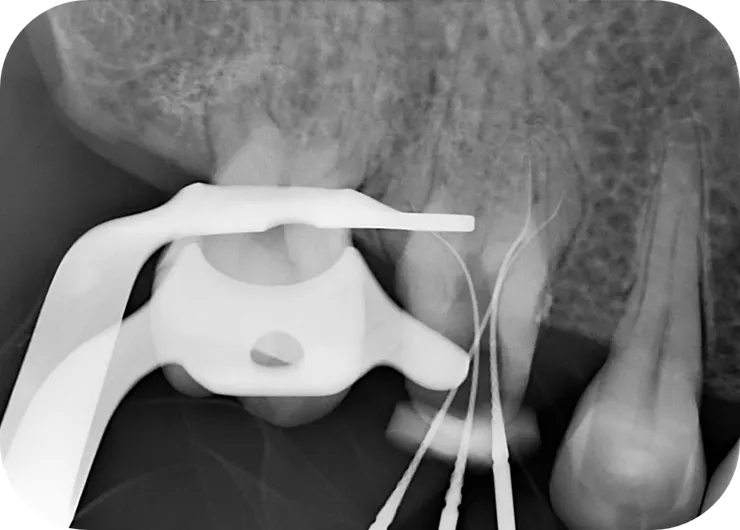

這篇的兩個主角分別是

左邊的 64 歲 16 (#20240611)

以及

右邊的 43 歲 26 (#20241224)

左圖:

確認 file 找到正確的路已順利過彎。

可以看到 file 中上段是 "自由"的。

右圖:

用 hand file 建立 glide path 後,後面的事就是小事了......